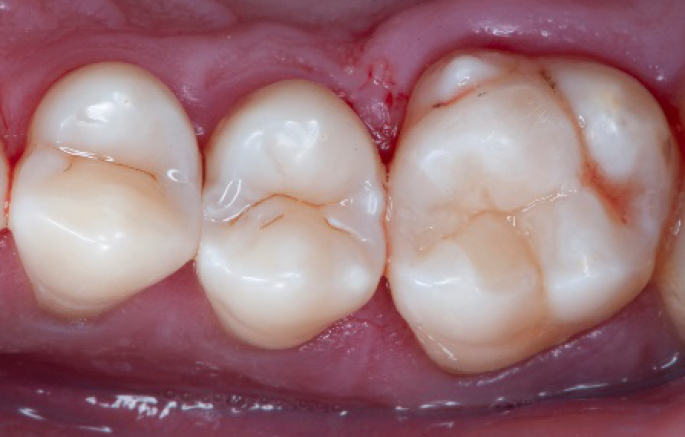

Step 3:

Class II cavity prepared.

Step 4:

The complete Palodent1 system in place: sectional matrix, wedge and ring.

Transformation of class II into class I, restoring the interproximal wall with Spectra ST4 composite in shade A2.